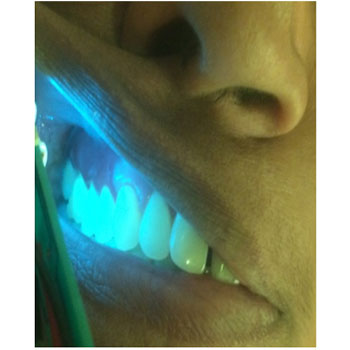

The intensity adjustability of the light gives additional advantage to the device in oral cavity where reflection with saliva and adjacent teeth is a common scenario .

CASE OF APTHOUS ULCER

CLINICAL IMAGE

FILTERED IMAGE

BLUE LIGHT IMAGE

BLUE LIGHT IMAGE FILTERED